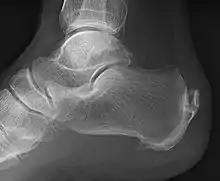

An enthesophyte, consisting of calcification deposits within the Achilles tendon at its calcaneal insertion. The Achilles tendon is wider than normal, further suggesting inflammation.

Enthesophytes are abnormal bony projections at the attachment of a tendon or ligament.[1] They are not to be confused with osteophytes, which are abnormal bony projections in joint spaces. Enthesophytes and osteophytes are bone responses for stress.[1]